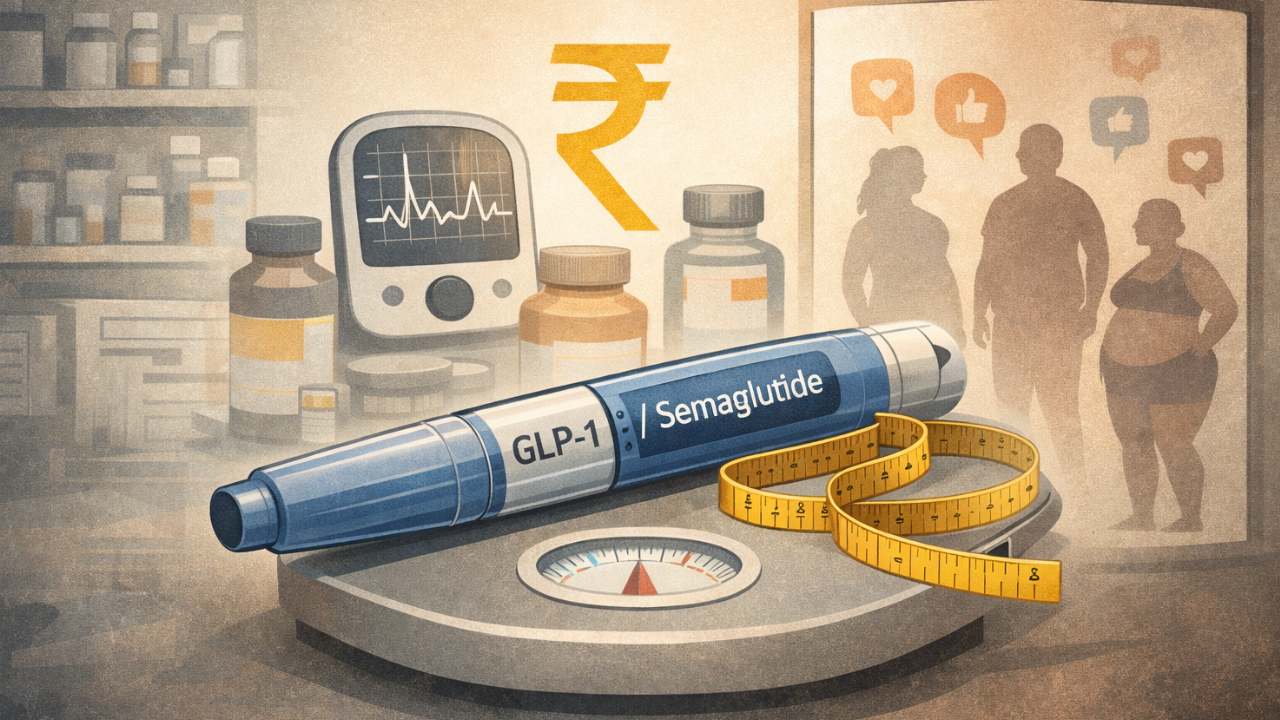

When Eric Stonestreet advocated Mounjaro

2025-08-04